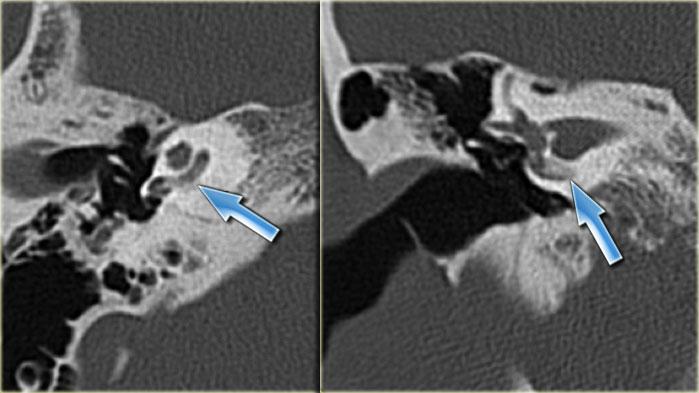

Bên trái là hình ảnh của một bé trai 16 tuổi, được khám tiền phẫu vì cholesteatoma tai phải.

Là một phát hiện tình cờ, có hình ảnh ống bán khuyên ngoài phình to (mũi tên vàng) và vắng mặt ống bán khuyên trên (mũi tên xanh dương).

Tại vị trí dự kiến của ống bán khuyên trên chỉ quan sát thấy một gờ nhỏ.

Ống bán khuyên sau bình thường.